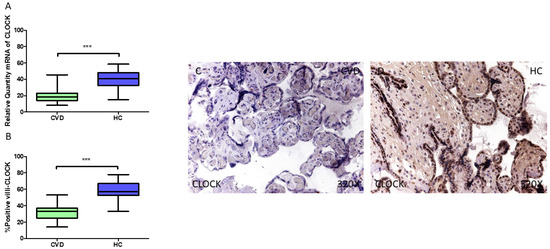

3.1. Placentas of Women Who Undergo Chronic Venous Disease During Pregnancy Display Decreased Expression of Key Circadian Markers